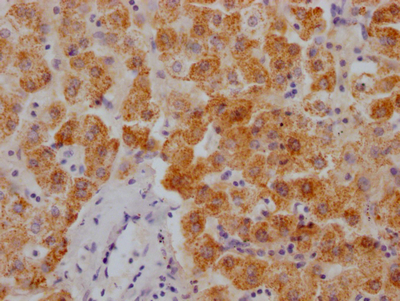

應用范圍:ELISA, IF

Application Recommended Dilution IF 1:50-1:200 -